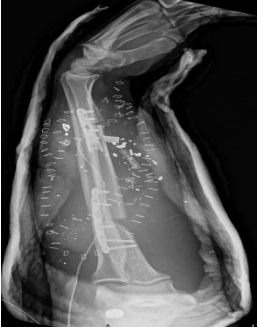

After appropriate debridement of the forearm wound, vertical osteotomies of the remaining native ulna were performed to create a landing zone for the free flap. The fibula was then affixed to the proximal and distal ends of the ulna with low profile reconstruction plates using monocortical bone screws on the fibula flap and bicortical bone screws to the native proximal and distal ulna. All the implanted hardware was appropriately covered with the fibula flap skin paddle and small skin grafts were used to cover the remaining soft tissue wound of the upper extremity and for closure of the fibula flap donor site. Radiographs following dressing removal at one week postoperatively showed good approximation of the free fibula flap interposed in the defect of the ulna.

Figure 4: A postoperative X-ray that illustrates adequate inset of the free fibula flap into the ulna defect and plated appropriately with good boney contact proximally and distally.